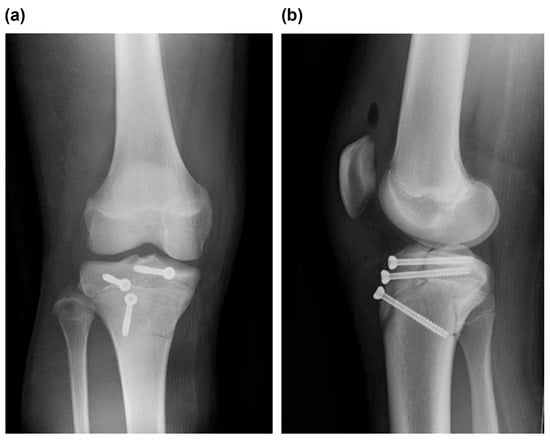

Type V Tibial Tubercle Avulsion Fracture with Suspected Complication of Anterior Cruciate Ligament Injury: A Case Report

2. Case Report